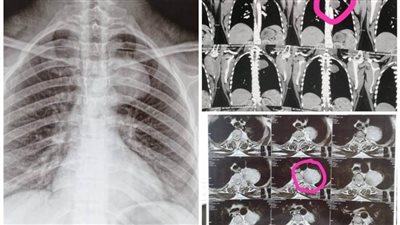

مستشفيات جامعة أسيوط تعلن نجاح فريق طبي بإنقاذ حياة أم وجنينها